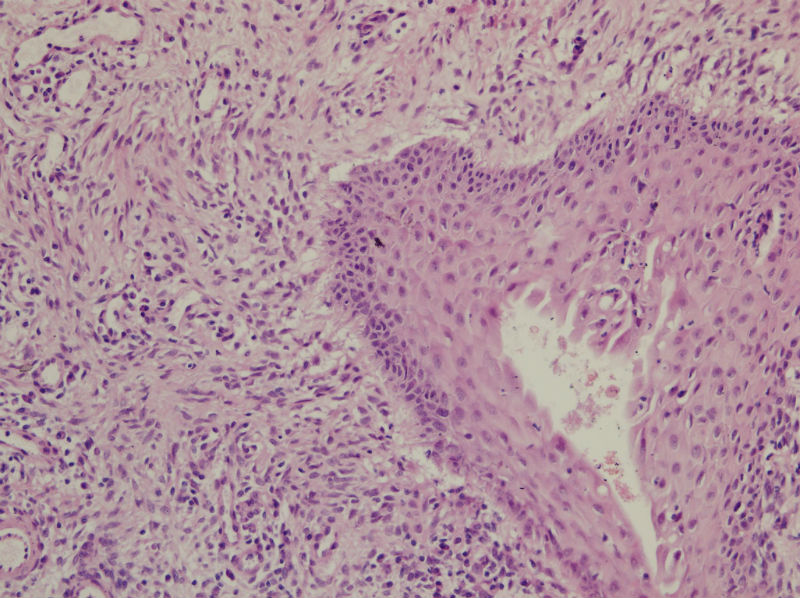

45岁,宫颈息肉?请老师指教

图2